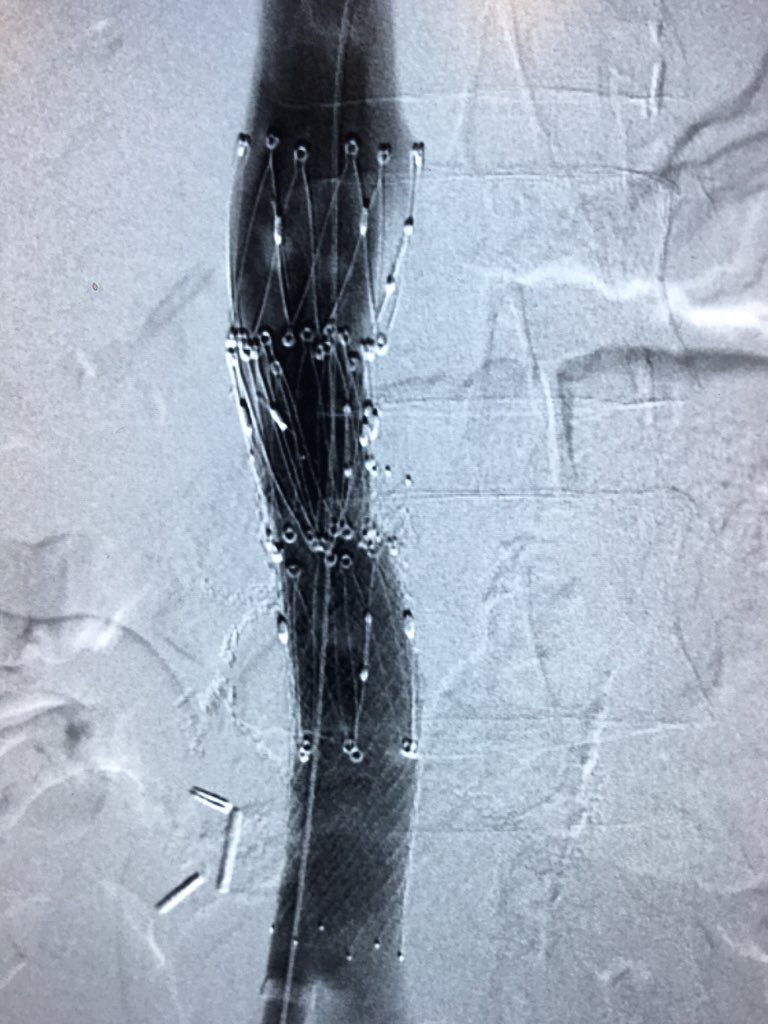

SubM PE. Post CDT refractory hypoxia, indigo aspirated RLL occlusion. Way better, although mPAP no change, others seen this often?